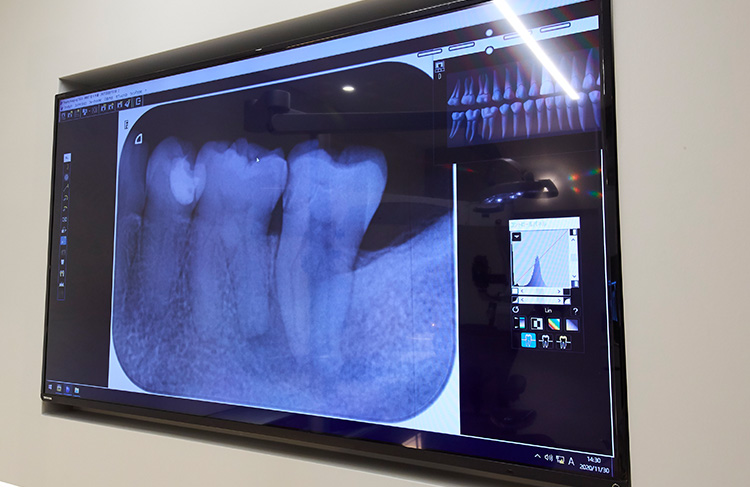

当院では全てのレントゲン機器がデジタル化されています。根管治療では術前から術後まで数回レントゲン撮影を行います。従来のレントゲンと比較し、低被曝のデジタルレントゲンで安心して治療を受けていただけます。

CTでは水平・垂直・斜めと見たい断面を自由自在に表示でき、立体的(3次元)な画像診断が可能となります。根管内は複雑な構造なので、輪切りの厚さや間隔を変えて撮影し、根管内の形状や側枝数、穴やまた破折等を見つけ、確実に疾患部の処置を行っていきます。通常のレントゲンでは判別できない小さな病巣も検出できます。